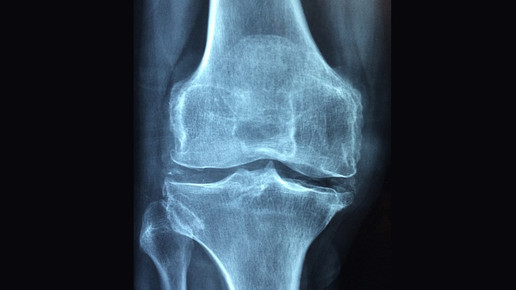

Nach Absetzen von Denosumab zur Behandlung einer Osteoporose kann es zu einem Knochendichteverlust kommen, der in einigen Fällen zu Brüchen führt. Derzeit ist noch nicht geklärt, ob die Knochendichte lediglich auf die Ausgangssituation vor Behandlungsbeginn zurückfällt oder es sogar zu einer überschießenden Gegenreaktion kommt, die zu vermehrtem Knochenabbau führt.

Wird Denosumab abgesetzt, sollte die Knochendichte immer wieder untersucht und eine Behandlung mit Bisphosphonaten in Betracht gezogen werden. Zur antiresorptiven Therapie bei Osteoporose eignen sich orale Bisphosphonate wie etwa Alendronsäure. Bei der Entscheidung für eine Behandlung mit Denosumab sollte die derzeit unklare Situation nach Absetzen der entsprechenden Medikamente berücksichtigt und mit den Patienten besprochen werden. Auch sind weitere Untersuchungen zur Ursache des Verlusts der Knochendichte und zu effektiven Gegenmaßnahmen erforderlich.

Der schnelle Knochendichteverlust nach Ende der Behandlung mit Denosumab sowie anderen Antiosteoporotika wie Teriparatid, die nicht auf Bisphosphonaten basieren, ist sei seit vielen Jahren bekannt, jedoch laut AkdÄ bislang in Produktinformationen oder Verordnungshinweisen nur unzureichend thematisiert worden. Bisphosphonate dagegen bleiben auch Jahre nach Beendigung der Behandlung im Knochengewebe, sodass je nach individuellem Frakturrisiko auch mögliche Therapiepausen über mehrere Jahre diskutiert werden.